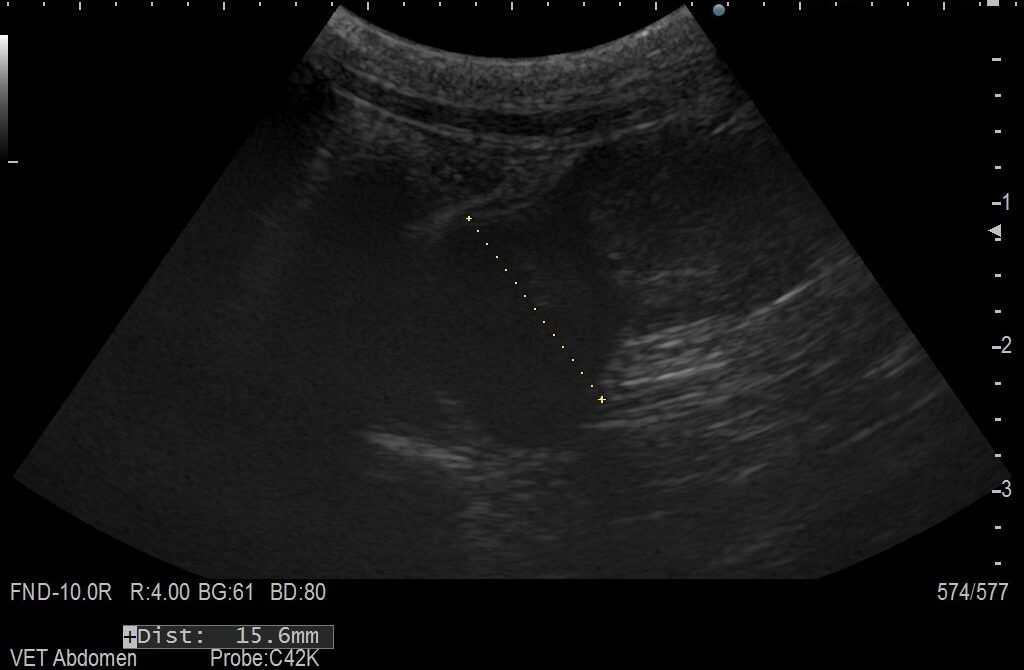

エコー写真① エコー写真②

超音波検査で見つかった子宮腫瘍